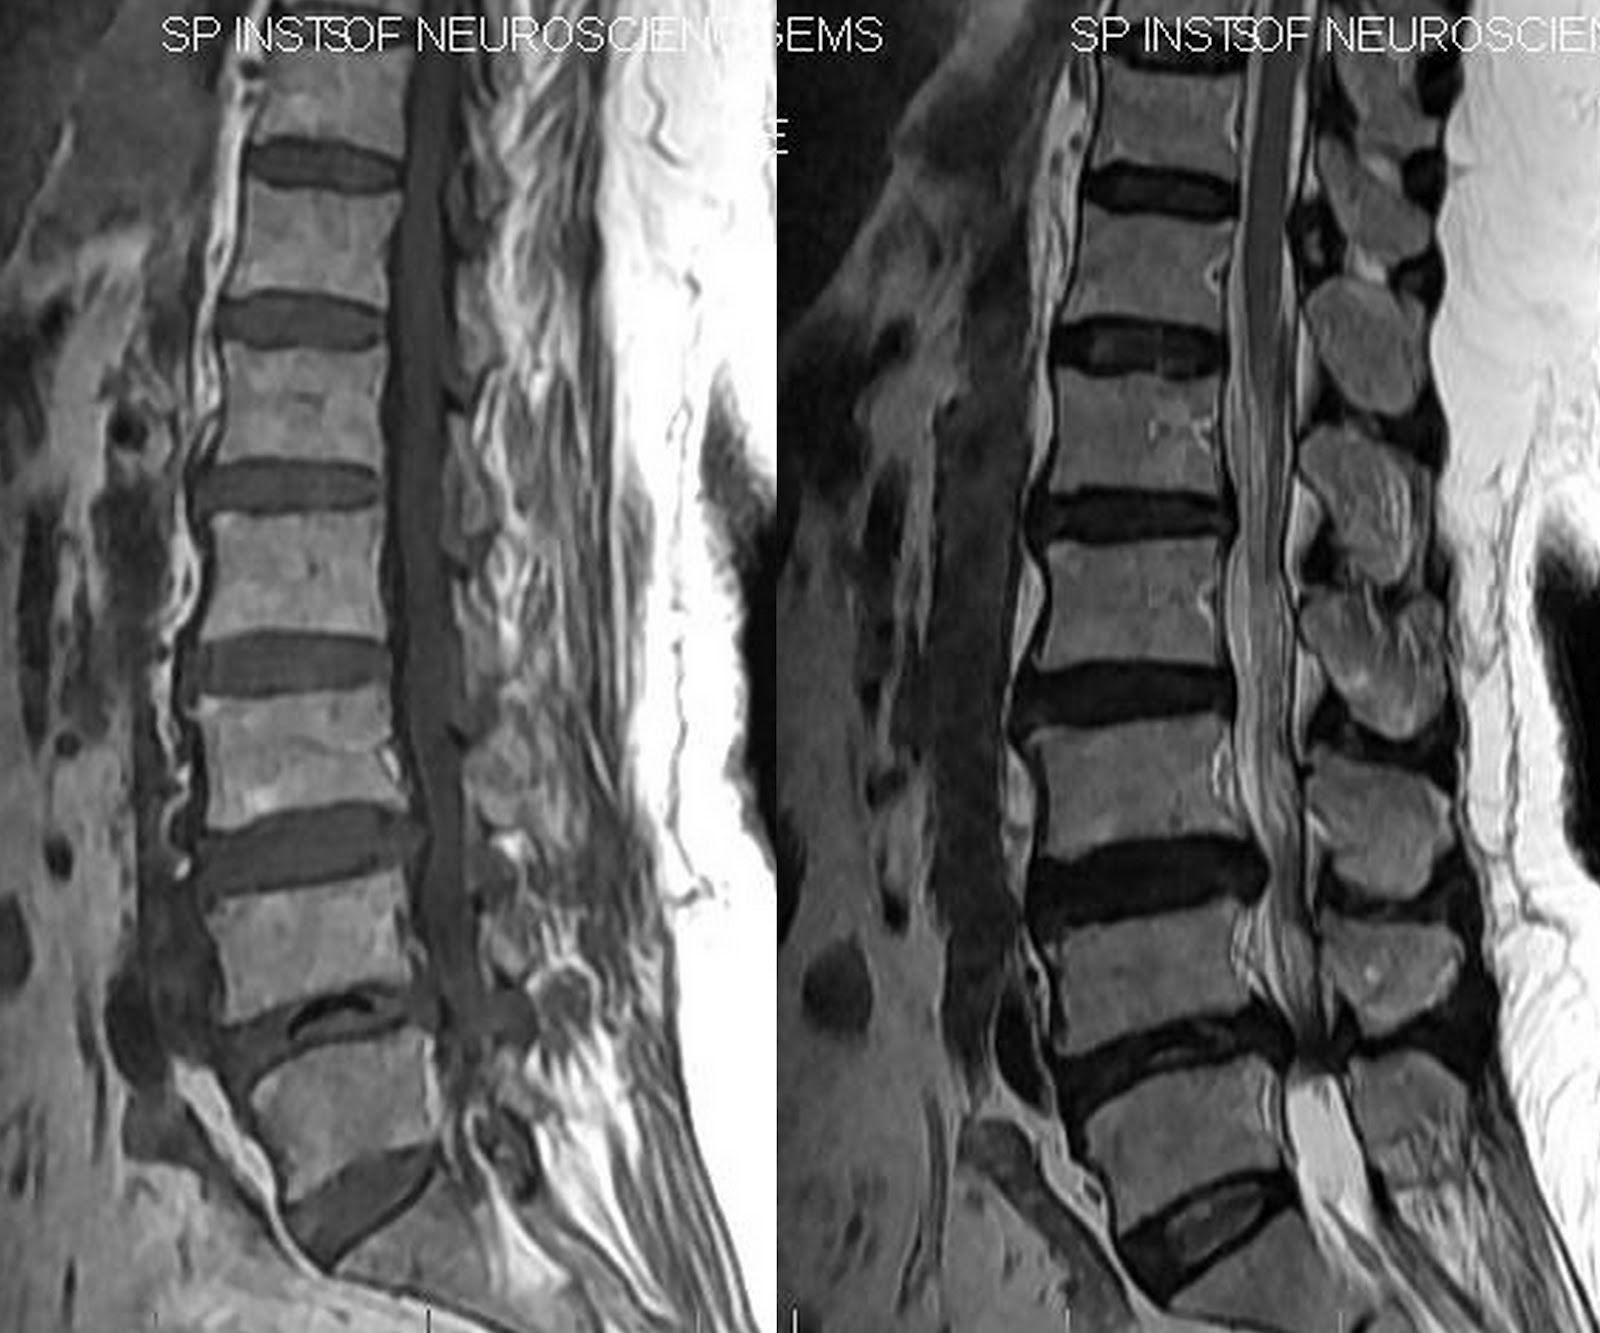

Discover the Vacuum Disc Phenomenon, a diagnostic sign in spinal imaging often linked to degenerative disc disease. Learn how this gas-filled radiolucent space appears on X-rays, its clinical significance in identifying intervertebral disc instability, and why it is a key indicator for healthcare professionals evaluating chronic back pain and spinal structural health in patients.